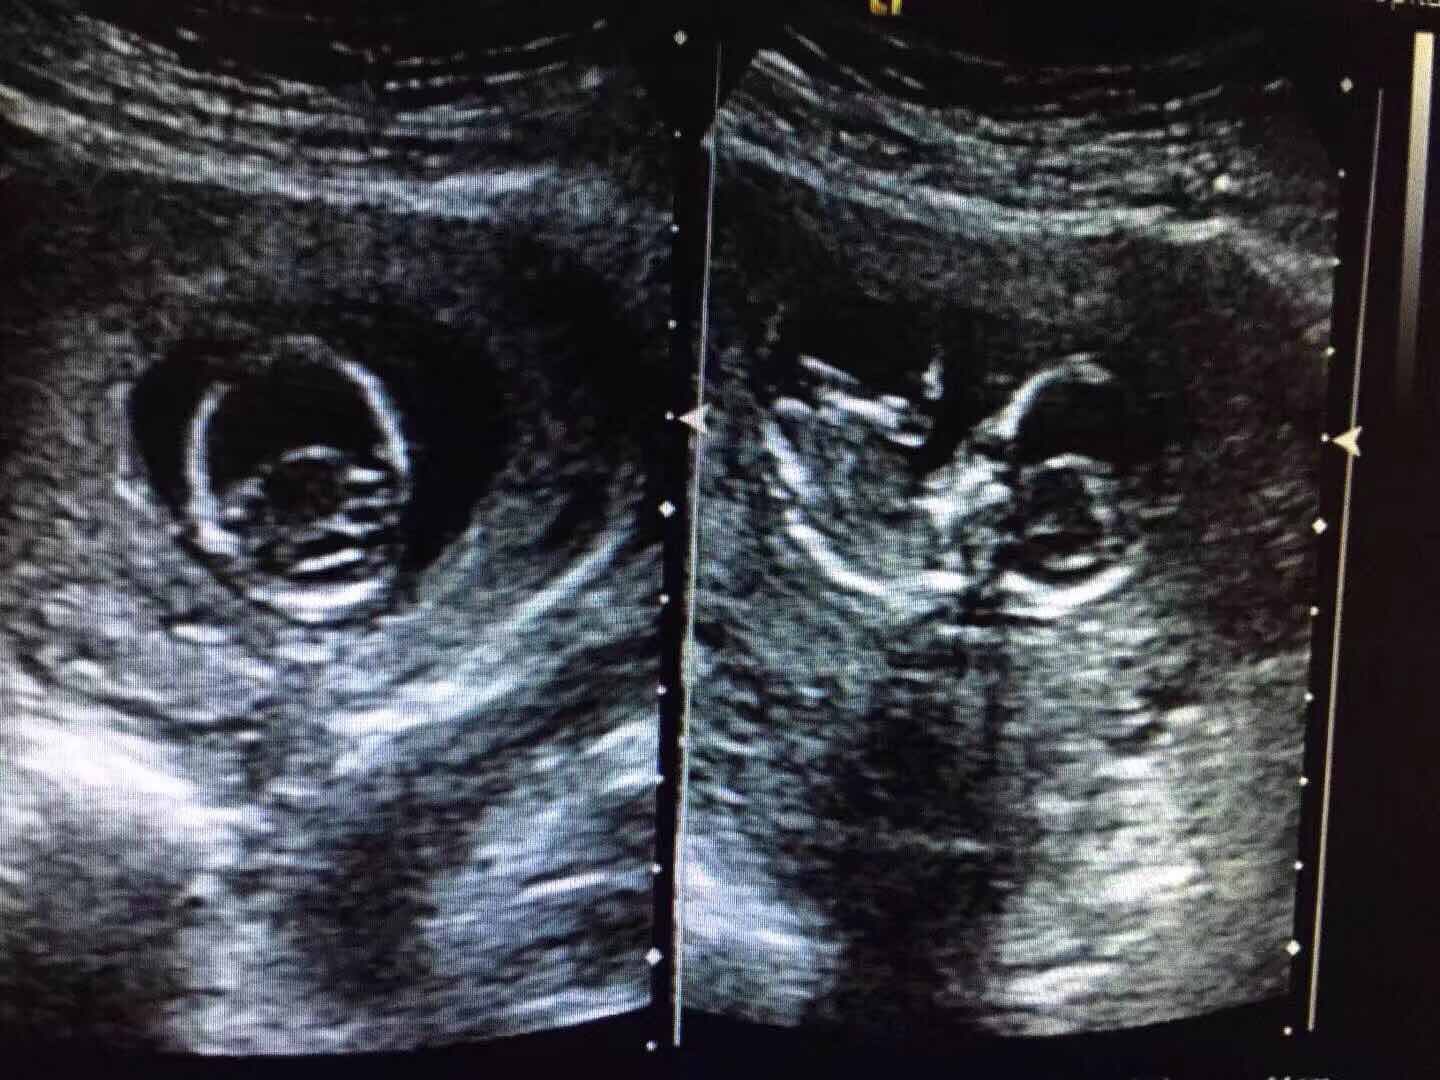

胎儿颅脑发育畸形:无叶前全脑

孕11+周,常规孕检。无任何不适,来院申请彩超检查发现异常。

颅骨光环可显示,前脑完全不分裂,呈单一脑室,丘脑融合,大脑镰、胼胝体,透明隔缺如,面部显示不清。